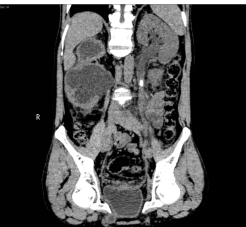

入院后,三维CT发现患者双侧输尿管结石,右肾盂输尿管连接处狭窄,右肾严重积水,左肾也因结石梗阻导致肾盂输尿管积水。肌酐1284.5μmoI/L,已经达到急性肾功能不全(尿毒症期)。王春阳教授立即为患者进行超声引导下右肾穿刺造瘘,改善患者肾功能,并制定拟行机器人辅助腹腔镜下双侧输尿管切开取石术+机器人辅助腹腔镜下右侧肾盂成型肾盂输尿管再吻合术,决定一次手术解决目前导致患者肾脏积水的全部问题。

王春阳教授介绍,仅利用一次手术同时处理患者全部问题,大大增加手术难度,但能减轻患者的痛苦和费用。对于结石大、梗阻明显、结石坎顿的病人,为及时解决梗阻,挽救肾功能,可选择输尿管切开取石。传统的输尿管切开取石手术疗效可靠,但患者手术创伤大,恢复慢,住院时间长。运用机器人辅助腹腔镜下行输尿管切开取石术不切断肌肉,不损伤较大血管神经,手术直视下进行,术野可放大10倍,手术损伤小,出血少,恢复快。同时该病人CT中表现出右侧肾盂输尿管连接部狭窄,切开取石后行右侧肾盂成形术,去除狭窄段,对肾盂输尿管连接部重新塑形,显著解除梗阻。